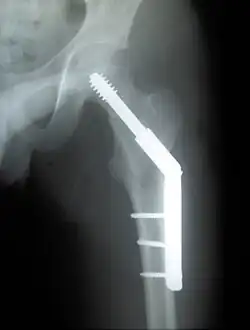

- in der Unfallchirurgie verwendete Materialien zur operativen Behandlung von Knochenbrüchen (Osteosynthese)